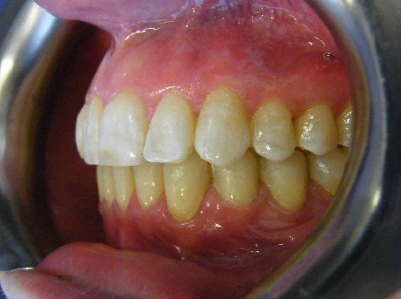

Patient 3: Severe upper and lower crowding.